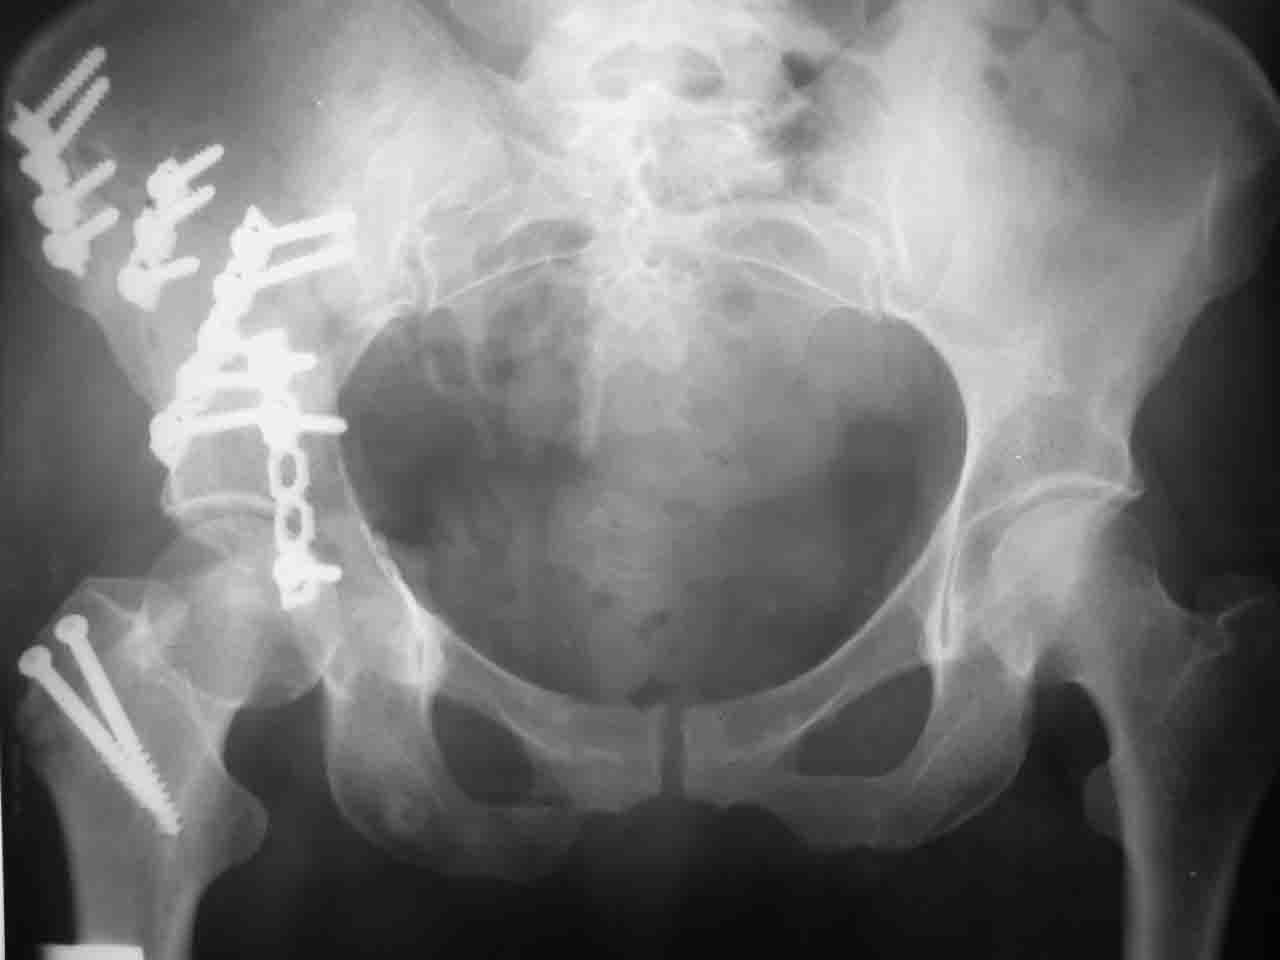

Re: Перелом вертлужной впадины

Снимки и схема